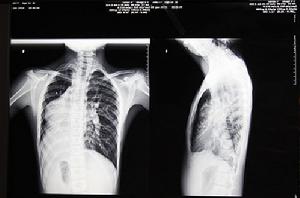

鏡面人X射線片“鏡面人”雖然內臟全部錯位,但只是位置發生變化,相互間的關係並未改變,因此生理功能與正常人一樣,對健康與生活都沒有太大影響。但值得注意的是,“鏡面人”一旦患病,醫生如果照常規判斷極有可能發生誤診。